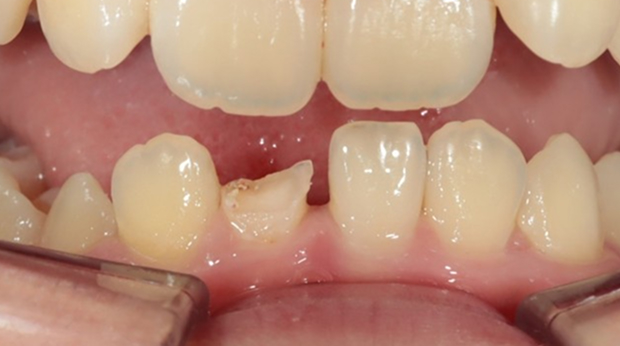

라미네이트